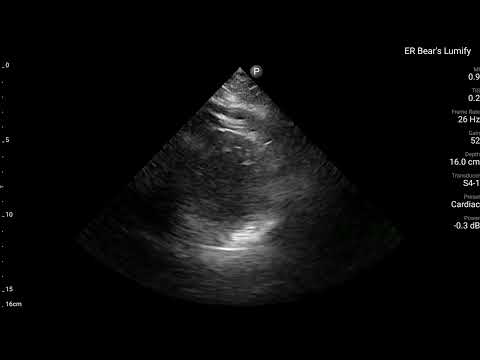

我們來看一下這位病患的POCUS影像

病患壯壯的,Image acquisition並不容易,不過可以隱約看到,Ant./Lateral/Inf wall都動得很不好,Septum收縮力還不錯!

綜合兩張的ECG finding、bedside echo看到RWMA at lateral/inf. wall